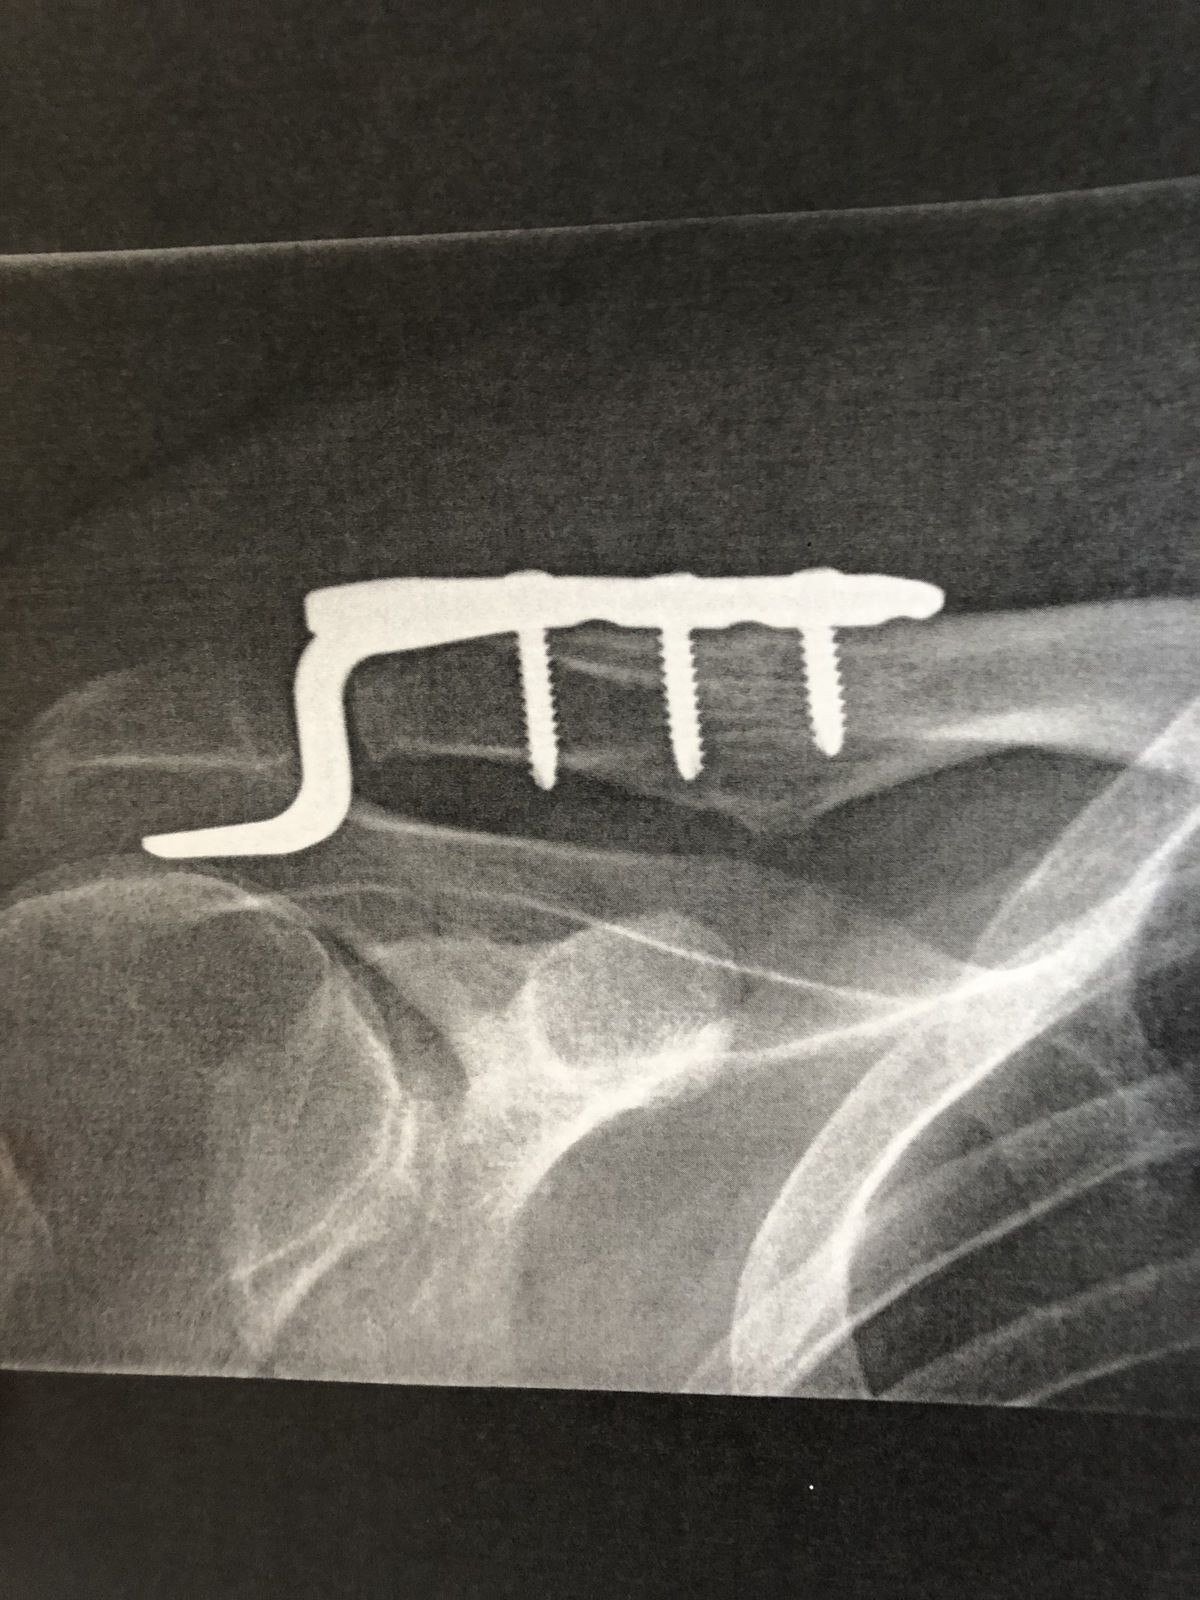

Ac luxation , nyckelben ur led

tittkorv sa:

En sån hook-platta hade jag under tre månader förra hösten när jag valde att operera min ac-lux grad 3. Med rehab och sedan vanlig träning i gym känns det helt ok i dag. I stort återställd med samma styrka och funktion som innan jag ramlade i backen. Kosmetisk blev det ju också bättre om man nu inte räknar ett stort ärr som negativt ?

Lycka till och som de flesta andra sagt så går det säkert bra oavsett hur du beslutar.